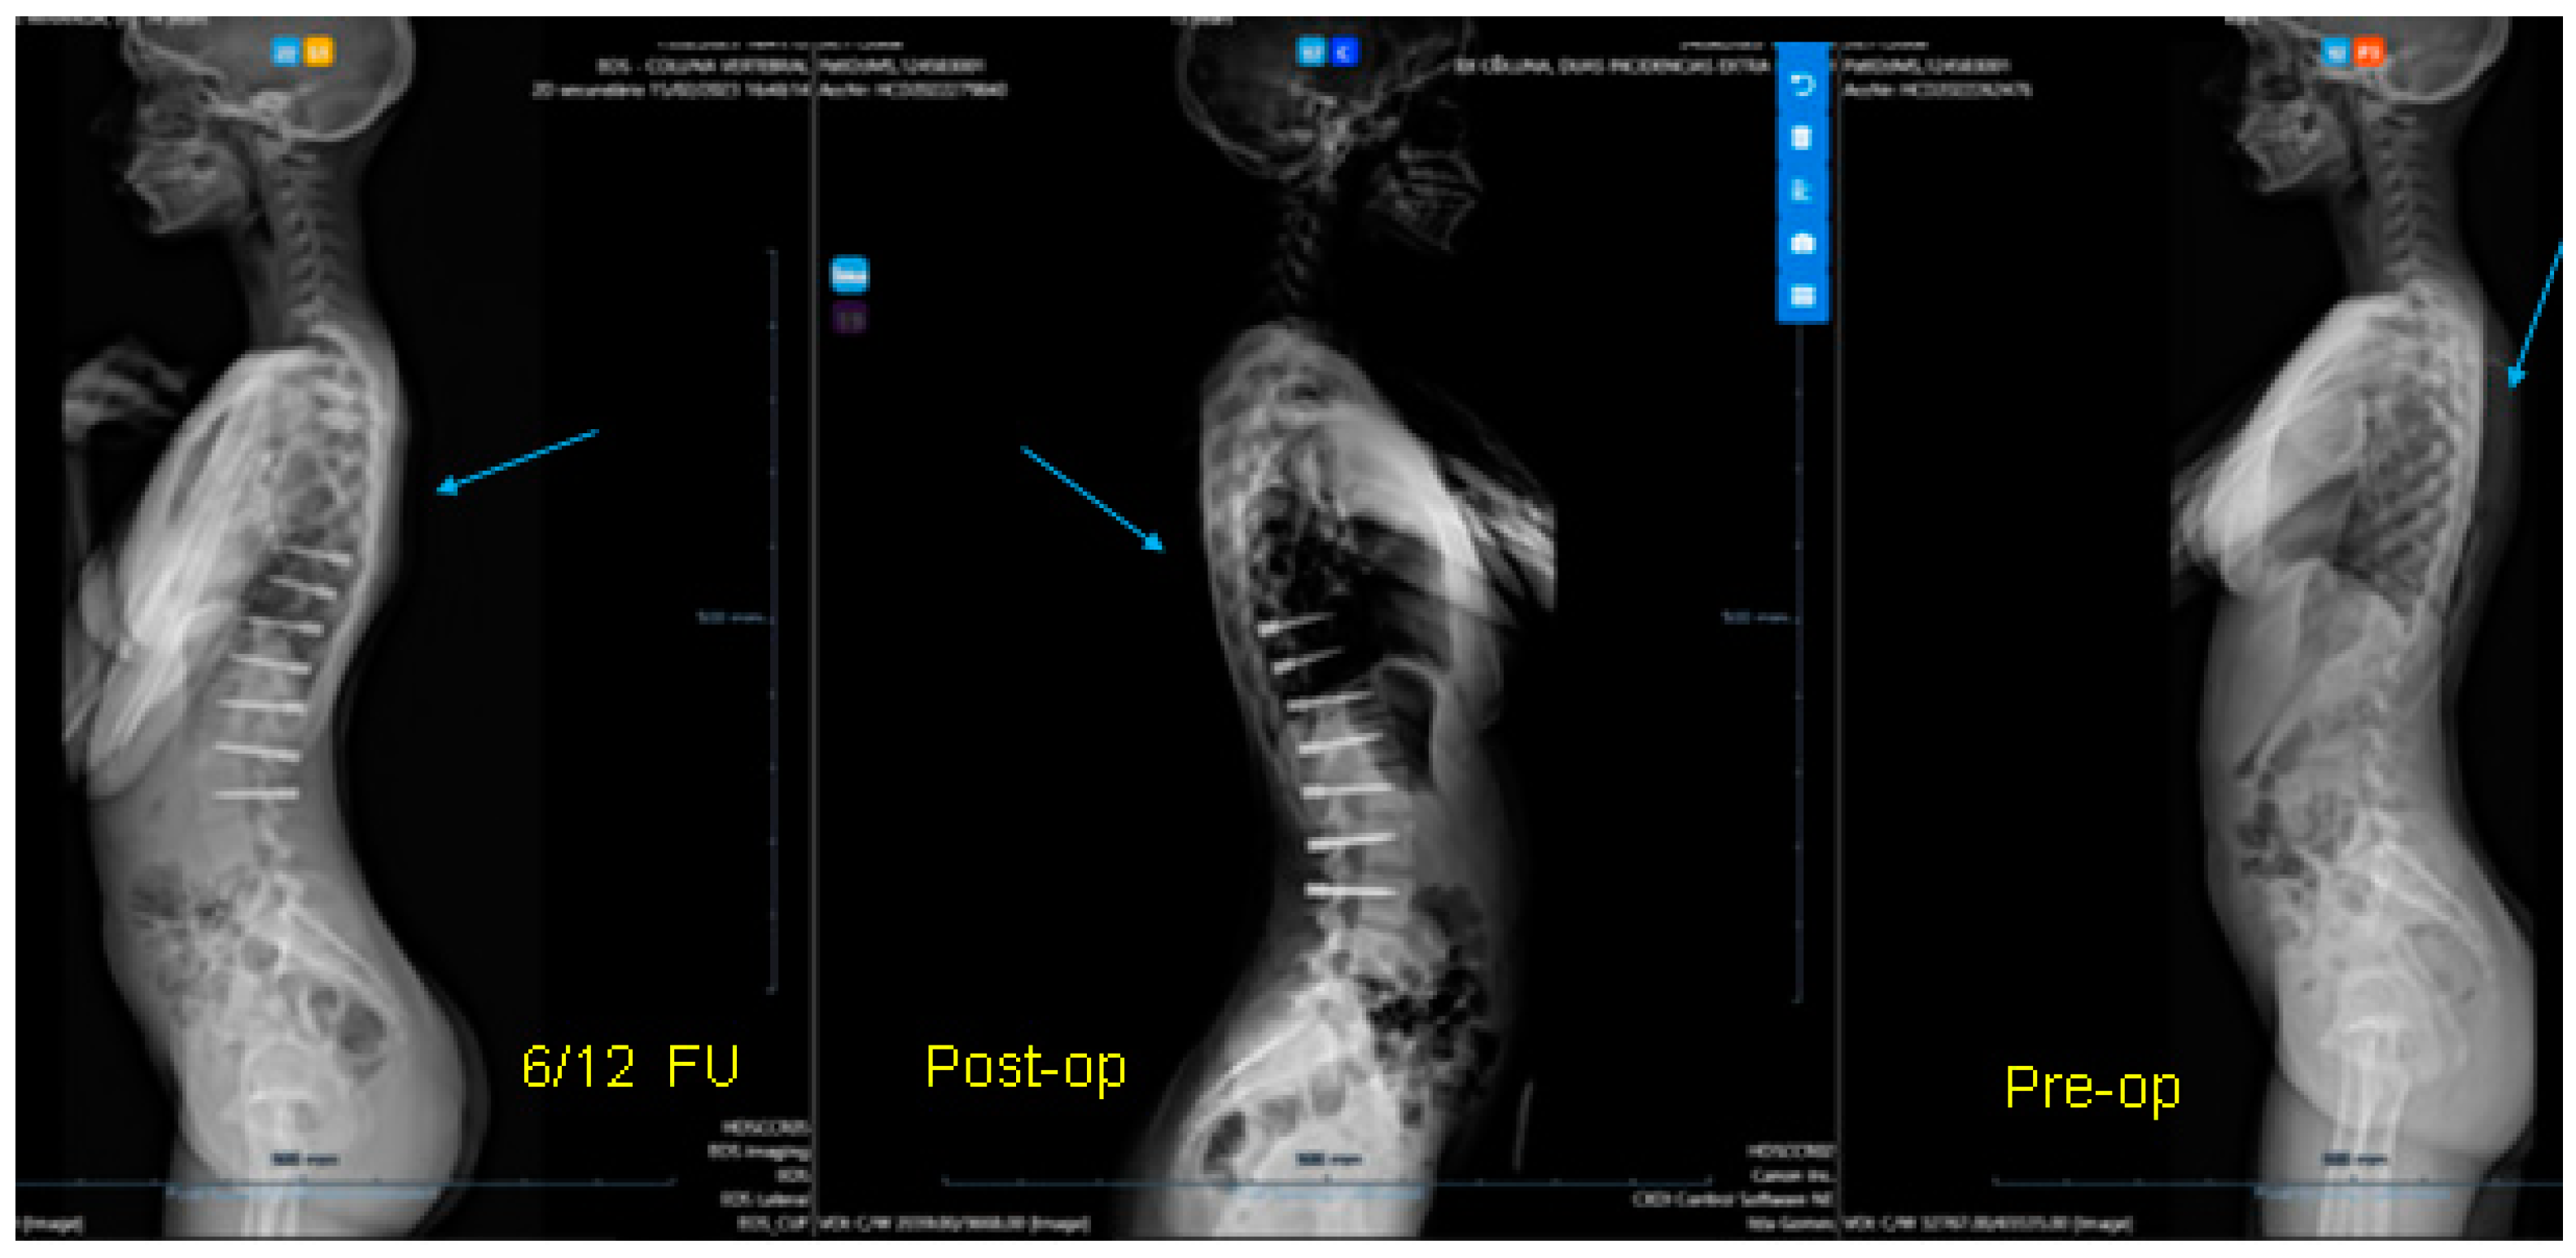

Figure 1.

(A) Thoracic scoliosis treated with Gruca Springs. (B) Double curve scoliosis treated with Gruca Springs.

From Mineiro’s archives (Figure 1), we can see that the posterior tether did work on the coronal plane for thoracic, thoracolumbar, and even double curvature scoliosis, but at that stage, orthopaedic surgeons were not concerned about the sagittal profile. Therefore, there are no lateral radiographs from these patients. In summary, looking back into the past, we can say that the posterior tether works for correcting the coronal scoliotic deformity in the adolescent growing spine (thoracic and thoracolumbar), but what would happen to the hypokyphosis of the spine in the lateral plane?